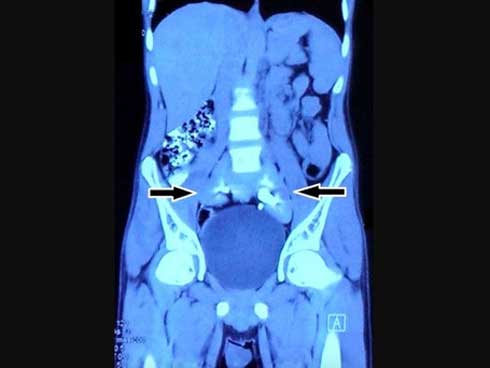

Cấu trúc tròn nhỏ giữa 2 mũi tên là quả thận bị hợp nhất của nam bệnh nhân - ảnh: BMJ Case Report

Thay vào đó, phía trên bàng quang của nam thanh niên có một cấu trúc kỳ lạ trông như một chiếc đĩa mà các bác sĩ điều trị chưa từng thấy trong cơ thể người.

Các bác sĩ đến từ Đại học Y khoa Maulana Azad (New Delhi- Ấn Độ) đã kiểm tra kỹ lưỡng hơn và xác định cấu trúc kỳ lạ kia chính là 1 quả thận.

Đó là một dị tật bẩm sinh khi còn trong bào thai. Không chỉ 2 quả thận bị nhập làm 1, nó còn nằm ở vị trí thấp hơn so với thận thông thường.